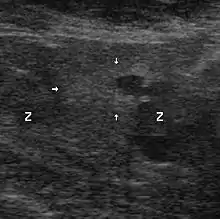

Échographie avec biopsies transrectales

Il n'existe actuellement aucun examen d'imagerie de pratique courante susceptible de détecter seul un foyer d'adénocarcinome prostatique avec une sensibilité et une spécificité satisfaisantes.

Contrairement à une idée encore largement répandue, et bien que cet examen soit ainsi encore souvent prescrit, l'échographie endorectale, seule, n'a pas d'utilité pour le diagnostic positif du cancer de la prostate, au regard du désagrément qu'elle est susceptible d'occasionner. Elle prend, en revanche, tout son intérêt lorsqu'elle sert à guider des biopsies prostatiques. Les autres modalités d'imagerie (scanner, IRM) ont un intérêt dans le bilan d'extension.

Technique

Une sonde d'échographie endorectale munie d'un guide d'aiguille est introduite dans le rectum. Les biopsies sont effectuées avec des aiguilles munies d'un mandrin encoché. Le mandrin pénètre le premier. L'aiguille vient le recouvrir, pour trancher et emprisonner ainsi le fragment de prostate situé dans l'encoche. Les mouvements du mandrin et de l'aiguille sont automatisés par un système de ressorts et le prélèvement est effectué en quelques centièmes de seconde. L'écran de l'échographe, muni d'un repère représentant le trajet de l'aiguille, permet, ainsi, des tirs biopsiques très précis.

Le nombre des biopsies, et l’endroit où elles doivent se faire, ne sont pas bien codifiés et de nombreux protocoles ont été proposés : le but est d'obtenir un échantillonnage aussi représentatif que possible. Actuellement, il est fréquemment réalisé 5 à 6 prélèvements par lobe, soit 10 à 12 au total. Ces nombres peuvent être diminués ou augmentés en fonction de la taille de la prostate, de la tolérance du patient, ou bien s'il s'agit d'une deuxième série de biopsies.